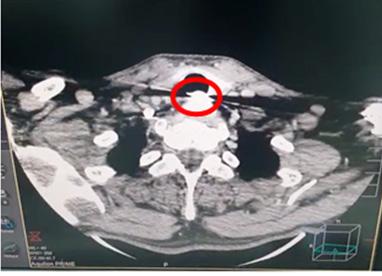

Trauma traqueal por migración de material de osteosíntesis de clavícula

Tracheal trauma due to migration of clavicle osteosynthesis material

Roly Ramos, Cristhian J. Guzmán, Rommer Ortega.............................................................................116-121